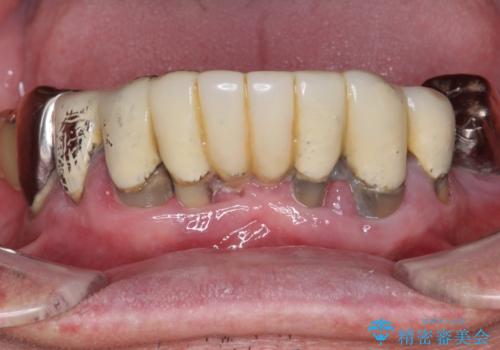

多発した虫歯による咬合崩壊 インプラントを用いた全顎治療

インプラント治療で達成するしっかりと食事できる噛み合わせ